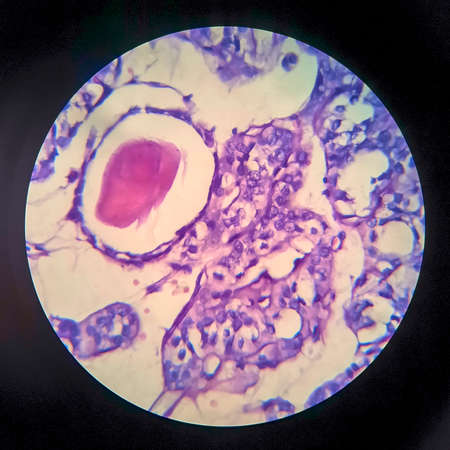

Light micrograph of teratoma, a tumor made up of several different types of tissue, such as hair, teeth, muscle, or bone. Teratoma is typically found in the ovary, testicle, or coccyx